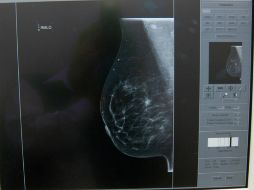

Tecnología Desarrollan en México chip para detectar cáncer de mama 25 de noviembre de 2014 - 10:17 hs Descubrimientos Ciencia médica